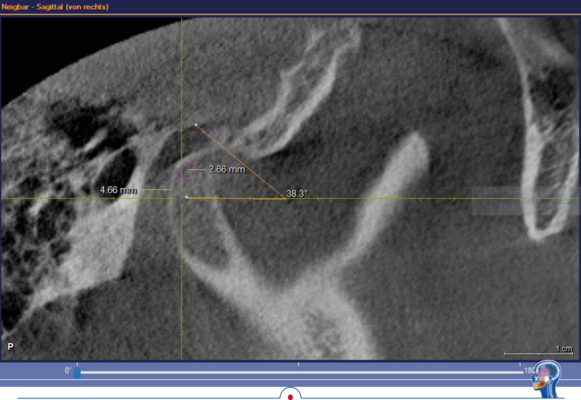

In dem hier vorgestellten Fall wurden diese Parameter zusätzlich im DVT bestimmt. Die im DVT ermittelte sagitale Gelenkbahnneigung beträgt rechts 41,9° und links 38,3°. Die mit Centric Guide® 3D ermittelte Gelenkbahnneigung beträgt rechts 43,86° und links 38,03°. Damit weichen die beiden Werte rechts nur um 1,96° und links nur um 0,27° voneinander ab. Wenn man sich die Gelenkbahneinstellung im Vollwertartikulator anschaut, stellt man schnell fest, dass diese nur in 5° Schritten erfolgt.

Mit der DVT Auswertung konnte nachgewiesen werden, dass die mit Centric Guide® 3D erfassten Parameter exakt mit der Anatomie des Patienten übereinstimmen. Kurz um man kann diesen Parametern definitiv vertrauen.